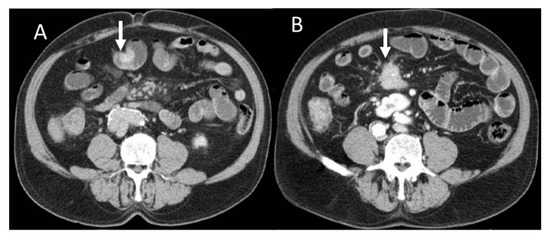

Figure 3.

CT evaluation during arterial phase of pancreatic NEN ((A): arrow) with liver metastases ((B): arrow).

In the presence of unclear imaging results in the diagnosis of PNEN, CT radiomics can be helpful in determining the type of tumor. In fact, PNECs in the portal venous phase on CT with contrast media tend to show greater uniformity and less entropy than PDACs in the absence of significant differences in these parameters in the arterial phase, kurtosis, and asymmetry (heterogeneity parameters) [63]. The cut-off value of 0.34 has been suggested for uniformity in differentiating NEC from PDAC with a sensitivity and specificity of 79% and 65%, and a cut-off value of 1.89 for entropy with a sensitivity of 74% and a specificity of 70% [63]. Radiomics is also particularly useful in differentiating atypical PNENs that show hypovascularization in the CT arterial phase from PDACs [64]. In fact, the latter have a greater skewness (which is a measure of heterogeneity) than atypical PNETs with lower mean, median, fifth, tenth, and twenty-fifth percentiles on the entire tumor structure by contrast-enhanced CT (CECT) compared to those of atypical PNET. The authors suggest that this result could be linked to a greater cystic necrosis and degeneration. The fifth percentile alone or combined with asymmetry was capable in differentiating the two groups with high sensitivity: when considered alone, a sensitivity of 96% and a moderate specificity of 64% were reached, while in combination, a sensitivity of 90% and a specificity of 80% were reached [64]. In another study, it emerged that a model of seven radiomic characteristics can differentiate between atypical PDAC and PNET with greater sensitivity and specificity than the model based on clinical radiological parameters alone [65]. Neuroendocrine tumors can be differentiated from adenocarcinomas by histogram analysis performed in DWI of apparent diffusion coefficient (ADC) values on MRI (Figure 4). PDACs showed greater kurtosis (heterogeneity marker) and skewness in ADC histogram analysis on ADC400 (b value 0–400 s/mm2) and ADC800 (b value 0–800 s/mm2) than PNET tumors, while neuroendocrine tumors, as seen in the analysis of the CT texture, have a significantly lower entropy, regardless of the b value [66].

Figure 4.

MRI assessment of pancreatic NEN. In T2-W (A) sequence, the lesion (arrow) is inhomogeneous and hypo–hyperintense due to fibrotic component. This feature is evident in late phase (B) of contrast study (arrow). In DWI ((C): b800 s/mm2), the lesion (arrow) shows restricted diffusion with hypointense signal in ADC map (arrow in (D)).